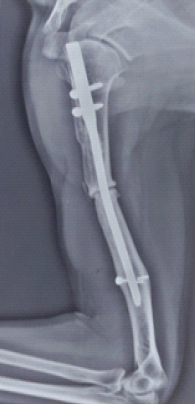

Twenty-year Delayed Failure of an Intramedullary Humeral Nail Due to Shaft Non-union and its Surgical Management: A Case Report

Akilan Soundararajan Narayanan , Soundararajan Karuppanan , Muthukannan Hari Sivanandan , Sudhir V , Vineeth B Maligi , Harsh Dinesh Chandak